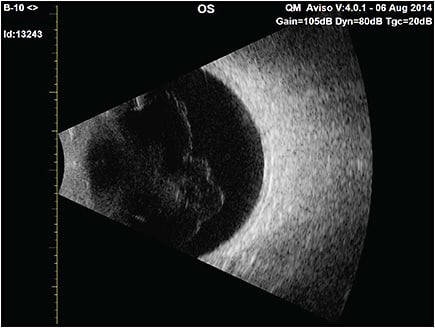

Although physical examination can image prominent vitreous opacities, there are limitations to the illumination-observation angle with slit-lamp biomicroscopy and no Tyndall effect with ophthalmoscopy. Ultrasonography is currently the best way to evaluate patients who complain of vitreous floaters, primarily because it enables evaluation of the entire vitreous body (Figure 5), not just the posterior aspects imaged by optical coherence tomography (OCT). Quantitative ultrasonography (QUS) was developed to provide objective assessment of vitreous density with a probe optimized for vitreous imaging.28 A clinical study showed that QUS measured greater vitreous density in subjects with PVD compared to controls without PVD, and that there is increasing vitreous echodensity and decreased CSF in the PVD group with increasing age,29 suggesting that not only do eyes with PVD have greater vitreous opacification than eyes without PVD, but that after PVD occurs, there is progressive aggregation of vitreous collagen fibrils in the vitreous body and/or increased folding of the detached posterior vitreous cortex, further degrading vision. Although imaging with sound is practical and useful, imaging with light would more closely approximate the phenomenon of VDM (Figure 4B and Figure 6). It is anticipated that technologies that measure light scattering26,30 in vivo will elucidate the mechanism(s) by which vitreous causes VDM. Ultimately, the goal is to provide therapies that reduce, eliminate, and perhaps one day prevent the deleterious impact of VDM on vision and quality of life. RP